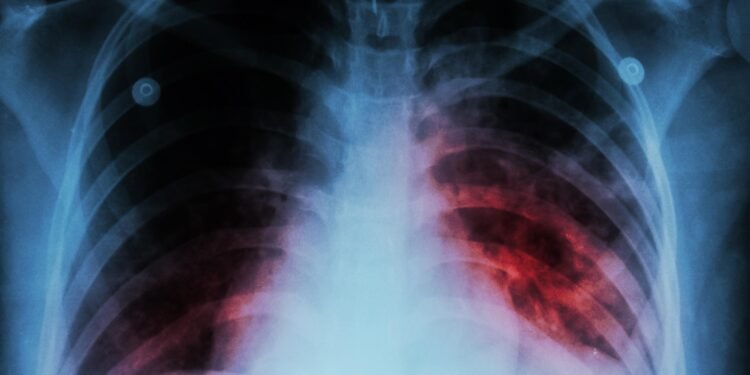

En cuanto a la detección, señaló que los estudios de expectoración permiten confirmar el diagnóstico en un periodo aproximado de 24 horas, complementados con estudios de imagen. Añadió que, en algunos casos, el antecedente de convivencia con personas infectadas resulta clave para la identificación oportuna.